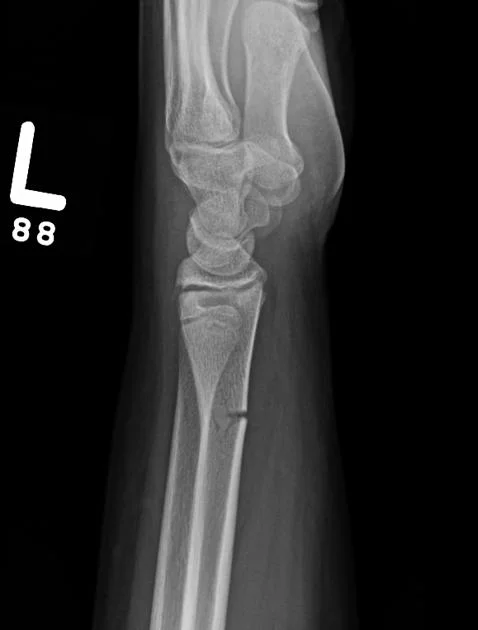

- Plain x-ray: (law of two s)

- Two views: AP and Lateral

- Two joints: joint above and joint below

- To show other injuries

- To assess rotation

- Two injuries

- e.g. patellar fracture and hip injury

- e.g. calcaneal fractures & spine injuries